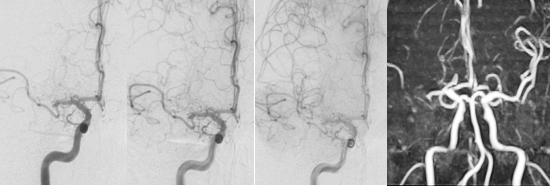

辅助检查:血常规、凝血功能、急诊生化均正常,免疫全项、甲功、血管炎抗体谱(-),心电图:正常窦性心律;心脏彩超:左室舒张功能稍减。头部MRI显示:右侧内分水岭区伴散在点状病灶。脑血管造影:右侧大脑中动脉(RMCA)狭窄、RMCA深穿支稀疏,右大脑半球的大部分由右大脑前动脉的软脑膜支反流供血。

图2. 入院脑血管造影